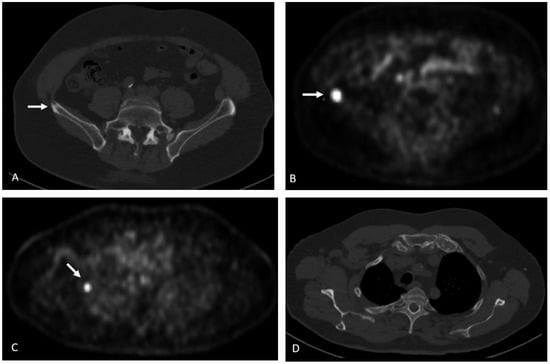

Detection of Loco-Regional Disease and Distant Metastases